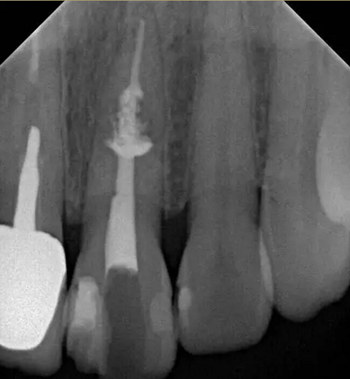

診斷:左上中切牙牙根內吸收。治療計劃:左上中切牙根管治療,全冠修復。 治療過程:患者知情同意。使用含1/100,000腎上腺素的4%鹽酸阿替卡因(碧蘭麻,艾龍)局部浸潤麻醉,橡皮障隔濕。去腐未盡露髓,露髓孔出血多。開髓,使用10#不銹鋼K銼(MANI,日本)探查根管,根管中段有鈣化物阻擋,不能達到牙根全長(圖3A)。在顯微鏡下(Leica M400E,萊卡, 德國) 使用超聲尖(E1根管治療超聲尖,啄木鳥公司,中國)通開,采用根管長度測量儀(Root ZX, Morita公司,日本)加診斷絲片法(圖1B)測量根管長22 mm。使用控制扭矩馬達(X-smart,登士柏)和鎳鈦旋轉器械(Hero 642, Micromega)根管預備,根管預備過程中使用5.25%次氯酸鈉溶液沖洗。 根備完成后使用超聲蕩洗根管,5.25%次氯酸鈉溶液3 分鐘, 17% EDTA溶液1分鐘。干燥根管,使用螺旋充填器根管內封氫氧化鈣糊,氧化鋅丁香油水門汀暫封。1周后患者復診,患者述無術后不適,檢查暫封完好,無叩痛,不松,牙齦無紅腫瘺管。使用橡皮障隔濕,去除暫封物,超聲蕩洗根管,5.25%次氯酸鈉溶液3 分鐘, 17% EDTA溶液1分鐘。干燥根管,牙膠尖(達雅鼎,中國)和必蘭根充糊劑(Cortisomol, 艾龍公司,法國)熱垂直加壓法根管充填。術后片顯示根充恰填,可見牙膠/糊劑被壓入鈣化物周圍和內部縫隙內